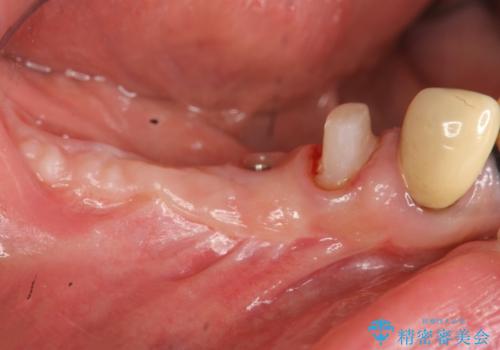

遊離歯肉移植術(硬い歯ぐきのインプラント周囲への移植)を行ったことで、炎症に強く歯ブラシのしやすい環境をインプラント周囲に整えることができました。

骨の造成、角化歯肉の移植を行いインプラント周囲の環境を整えた治療を計画します。